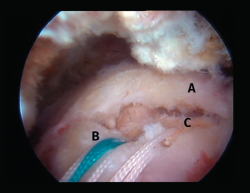

Figura 4. Rotura de supra- e infraespinoso en forma de L invertida con presencia de 2 capas. A: tendón supraespinoso; B: tendón infraespinoso; C: cabeza humeral.

Figura 5. Rotura de tipo C1. A: rotura pequeña de espesor completo del supraespinoso; B: cabeza humeral.

Sin embargo, las clasificaciones basadas en el tamaño de la rotura deben ser bidimensionales, ya que la visión unidimensional puede ser engañosa, al mostrar el tamaño de la rotura solo desde el plano anteroposterior(4). Por esta razón, proponemos el sistema de clasificación del manguito posterosuperior sugerida por Snyder, que aporta información no solo del tamaño, sino del número de tendones afectados y la presencia de tejido cicatricial(7). En las lesiones de tipo C1 la lesión atraviesa todo el espesor del tendón y en el eje transversal es pequeña y punzante (Figura 5). Las de tipo C2 son roturas de espesor completo pero la distancia entre los extremos de la rotura es menor de 2 cm con escasa retracción (Figura 6). En las de tipo C3 la rotura afecta en sentido transversal entre 3 y 4 cm con mayor retracción implicando 2 tendones (Figura 7). Y las de tipo C4 son la rotura masiva del manguito de los rotadores con una afectación de espesor completo de toda la anchura de 2 o más tendones asociando importante retracción (Figura 8).